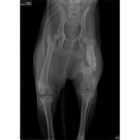

The injury she suffered was pretty bad, and it was never properly cared for, so she will need a plate in her hip to fix the fracture and help her to be able to walk and not be in pain. The other option is amputation. The cost of the surgery is $2,200 – $2,400, plus any pre- and post-surgery care.